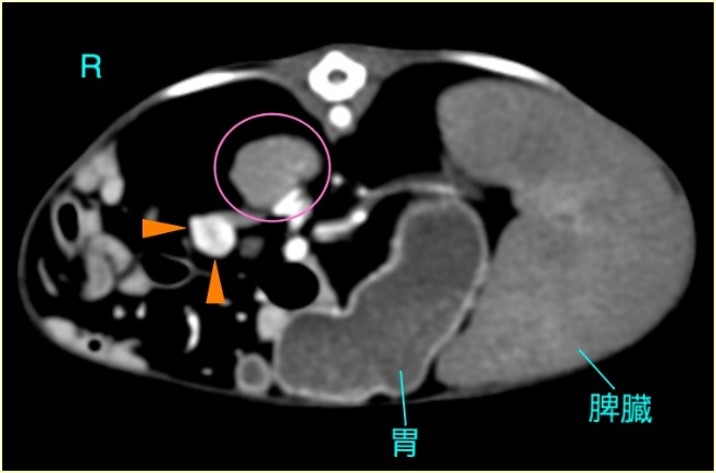

インスリノーマは特異的な症状と血液検査で低血糖の確認をします。膵臓に発生した腫瘍の多くは数mmのサイズなので、レントゲン検査や超音波検査ではみつかりません。詳細はCT検査になります。

大きな痙攣発作が起こるフェレットには有効かもしれません。外科手術を行うならばCT検査をすることをお薦めします。腫瘍は目にみえないほど小さいこともあり、また複数に発生している場合は、全部が摘出できません。せっかく麻酔をかけて、あまり摘出できなかったということもあります。大きな腫瘍である場合は、それを摘出することで痙攣発作がおさまることが多いです。